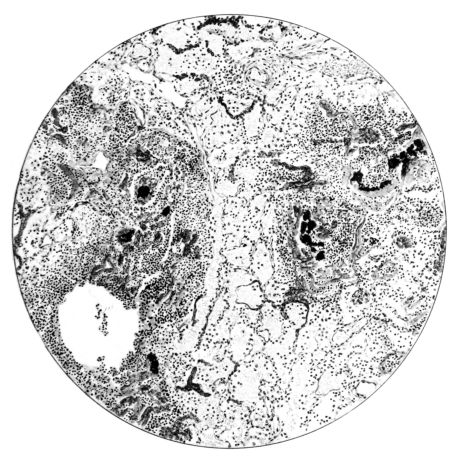

No matter what the portion of the lung from which the sections are derived, the fundamental changes found are the same. The subpleural sheets are spread wide apart, now by empty spaces, now by coagulated fluid. The process extends from the surface through the interlobular septa (Fig. XX), and is accentuated where the connective tissue is more prominent around vessels and bronchi. The nature of the infiltrate in the subpleural and interstitial tissues becomes more evident in the alveoli, which likewise are filled. The material varies somewhat in appearance, probably dependent upon its proteid content. Not infrequently the alveoli contain a homogeneous, pink-staining mass, which resembles the colloid of the thyroid gland. Again, it may be simply a coarse granular precipitate (Fig. XXIII), and in still other instances, small sticks and strands form the bulk of the alveolar content (47, 92, 140, 156). This subpleural, interstitial, perivascular, peribronchial, and alveolar edema, which is a term applicable to this collection of fluid, is very prominent, and although its intensity varies in different portions of the lung; and although it may be replaced in some areas by other types of exudate, unquestionably, this is the dominating expression of the inflammatory process in the early stage of the disease.

As might be expected from the gross appearance, the alveoli vary in size. At times slightly collapsed and at other times overdistended, their lumina are still the seat of the inflammatory exudate, although the mechanical change may allow of some variation in the appearance of their walls. As a rule, however, the alveolar wall is prominent and owes its conspicuousness to the tortuous, engorged vessels within. These vessels contain red blood cells almost exclusively, and on account of the partial, occasionally complete, loss of the lining epithelium, the alveolar wall appears as a huge, dilated arteriole (101) separating the lakes of coagulated material in the spaces (Fig. XXIII). There are areas, as indicated above, where the alveolar content may be more definitely arranged in the form of beaded or homogeneous strands of different caliber; the smallest resemble delicate threads. They tend to converge toward the alveolar wall like wheat in a sheaf, and often pass through this wall by way of the so-called pores of Cohn; as soon as the body of the neighboring alveolus is reached, they again present a fan-like expansion into innumerable, fine strands (Fig. XXII). Where the exudate is more fibrinous, the alveolar wall is less likely to be distended, its vessels are not so prominent, and their content of red blood cells is definitely decreased. Still this is not the most extreme type of alveolar exudate met with at this stage. Perhaps, the most striking, although not the most frequent, exudate has a superficial resemblance to a huge, red blood clot, and it may be difficult to make out the alveolar walls separating the masses of well preserved red blood cells that fill the alveolar spaces. These areas are indistinguishable from infarcts and may be associated with thrombotic arteritis in near-by pulmonary vessels (47) (Figs. XXIV and XXV). Among the red blood cells an occasional strand of fibrin, a desquamated alveolar epithelial cell, and rarely a polymorphonuclear leucocyte may be encountered. The alveolar wall itself varies in the definition of its outline. When its vessels are greatly distended, when its alveolar epithelium is gone, and when its content consists largely of red blood cells, it is difficult to distinguish from the exudate which it encloses. However, when it is more compressed or when its epithelial lining cells are still more or less intact, it may be seen as a blue-staining strand under the low power of the microscope, for the well preserved nuclei lend it prominence.